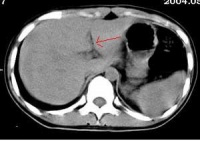

三、影像学表现[编辑 | 编辑源代码]

胃肠道穿孔的主要X线表现是气腹即腹膜腔内出现游离气体。关于气腹的显示方法,一般是采用透视与照片检查。尤其是少量气腹的显示则尤为重要,如病情允许,立

位透视并转动体位观察,此时往往能显示膈下新月形的游离气体的存在,因为气体总是具有浮游到腹腔最高处去的倾向,确定了膈下游离气体后,应即时照片以供临床参考。

在病情危重而不能坐或站立时,可采用仰卧侧位投照,此时气体可上升至前腹侧壁,可以见到腹壁与肝和肠之间有气层,使肝前下缘和肠外壁显示。

如情况只允许照仰卧位片时,只要能详细地认真阅片,亦可能发现有价值的征象:

一是见到明确的腹腔内脏器(胃肠和肝脾)的外壁;

二是腹腔内某些韧带(如肝脏前力的镰状韧带)的明确显示。见到这些征象

应考虑有气腹存在。如无气腹发现而临床又高度提示有急性胃肠道穿孔时,必要时可经胃管抽吸胃液后注入空气约300ml,则空气可从穿孔处逸出形成膈下游离气体,有助了胃、十二指肠溃疡穿孔的诊断。

长期以来,气腹是放射医师诊断胃肠道穿孔的依据并为临床医师所接受。但气腹并不一定都是胃肠道穿孔或破裂所引起,亦可见于腹部手术后,子宫及附件穿破,产气细菌腹内感染和肠气囊肿并发破裂等。